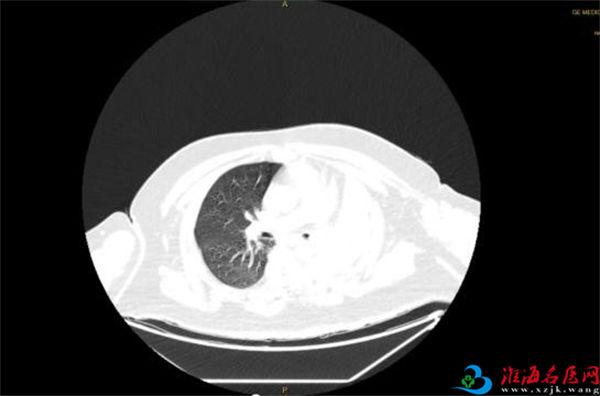

4月14日,王先生因“憋喘伴发热咳嗽半月余”到徐医附院急诊就诊。据王先生家人介绍,患者半个多月来,憋喘不断加重,先后在我市多家医院就诊,考虑左肺不张伴感染,但通过积极抗感染治疗,憋喘无改善并逐渐加重,同时出现发热症状,体温最高近39摄氏度。徐医附院呼吸与危重症医学科何军主任会诊后,考虑患者智力异常,进食方式特殊,不排除误吸的情况,阅片后发现左主支气管内存在异物可能,需行气管镜检查进一步明确肺内情况。考虑患者一般情况差,存在I型呼吸衰竭,肺部感染重等情况,于是将其收治在呼吸重症监护室(RICU)。

患者入院后进行高流量氧疗和抗感染治疗,因为其肥胖合并呼吸衰竭,肺部感染重,气管镜风险高,在与家属充分沟通后,呼吸ICU团队于4月15日为王先生行床旁气管镜检查,镜下发现左主支气管内一白色圆形异物,表面为坏死覆盖,清除坏死组织后,异物质硬,表面光滑,无法钳取。同时患者病情危重、麻醉评估风险极高,在陈碧主任的主持下,呼吸ICU团队经过讨论后决定行床旁气管镜取异物术。

季磊副主任医师在杨翌、蒋宇及刘慧医师的协助下,在全麻下经气管插管(8#)套管进镜,左主支气管内可见被粘痰、坏死物包裹一圆形异物,清理后发现异物为花生粒,长径约2cm,由于花生粒过大,无法通过8#气管导管,于是将花生粒分解,通过使用圈套器、异物钳以及网篮逐一将其取出,总共历时1.5个小时。取出异物后,左主支气管及其分支可见大量黄色脓性分泌物,予以充分吸除。后续给与积极抗感染等治疗,复查胸片示左肺不张改善,体温正常,炎症指标下降,再次复查气管镜下可见痰量较前明显减少,总体病情好转,4月23日转到普通病房继续治疗。患者家属表示,辗转三家医院就医,还是徐医附院最值得信任,对呼吸ICU全体医护人员表达了敬意和衷心感谢。